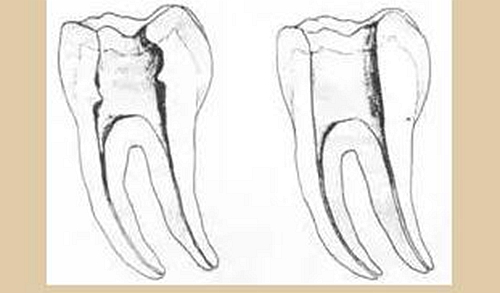

三、開(kāi)髓孔

1. 正常開(kāi)髓孔的位置和大小

左圖為正常開(kāi)髓孔的大小和位置。左邊圖為下顎,右邊圖為上顎。

2. 根管治療中開(kāi)髓孔的設(shè)計(jì)標(biāo)準(zhǔn)

根管治療需去除髓腔內(nèi)容物(去除髓室頂),建立所有根管的入路,允許沖洗液大量沖洗。開(kāi)髓孔的設(shè)計(jì)標(biāo)準(zhǔn)以建立通路為目的,從而建立良好的視野和術(shù)野。

( 1 )直線通路:根管治療時(shí)需要一個(gè)直線通路,直線通路能夠達(dá)到根尖三分之一

測(cè)量標(biāo)準(zhǔn):以允許根管器械直線并直接進(jìn)入根尖 1/3 且不接觸冠方各壁為標(biāo)準(zhǔn)。

( 2 )髓腔其他改變:如髓室頂、繼發(fā)性牙本質(zhì)、修復(fù)性或增齡性牙本質(zhì)。見(jiàn)左圖。

右圖中有繼發(fā)性牙本質(zhì),切削后獲得直線通路。